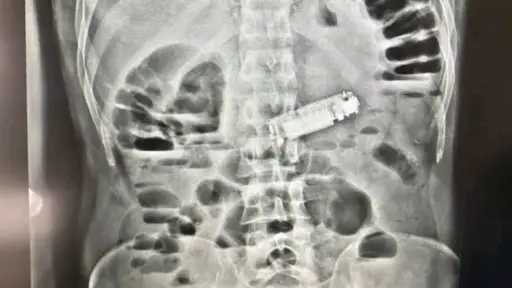

وعلى أمل أن يكون الورم حميدًا وأن تكون الأزمة قد انتهت، عادت مريم مع أحمد إلى حياتهما الهادئة، لكن القدر كان يخبئ لها صدمة جديدة. زيارة مفاجئة من عاليا في مكان عملها بالمكتبة، تحمل إليها الحقيقة القاسية وهي الورم خبيث.